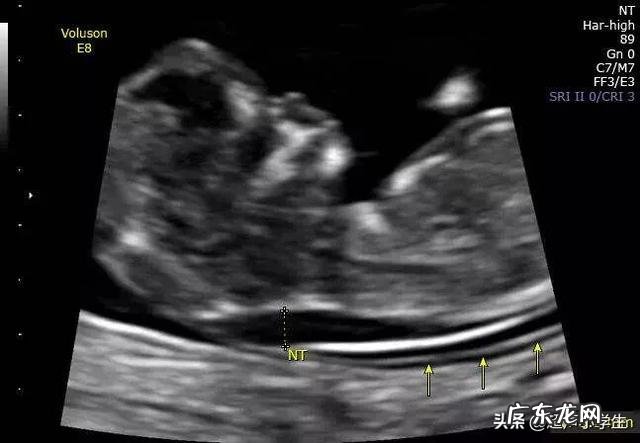

测量NT一般在胎儿11-13周6天时候检查 , 测量数值为2.6mm , 会提示胎儿NT高值 , NT高会有唐氏儿的风险 , 所以为了让自己更放心 , 建议做无创DNA检查 。

把握好NT检查的标准 , 就知道NT值是2.6mm是正常的 。

NT值区别于其他检查数据 , NT值只要小于3.0mm都属于正常值 。所以NT值为2.6mm就意味着属于正常 。